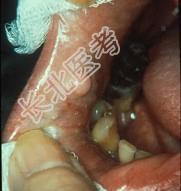

单项选择题组图为口内纤维瘤的外观,关于此病的描述不正确的是 ( )